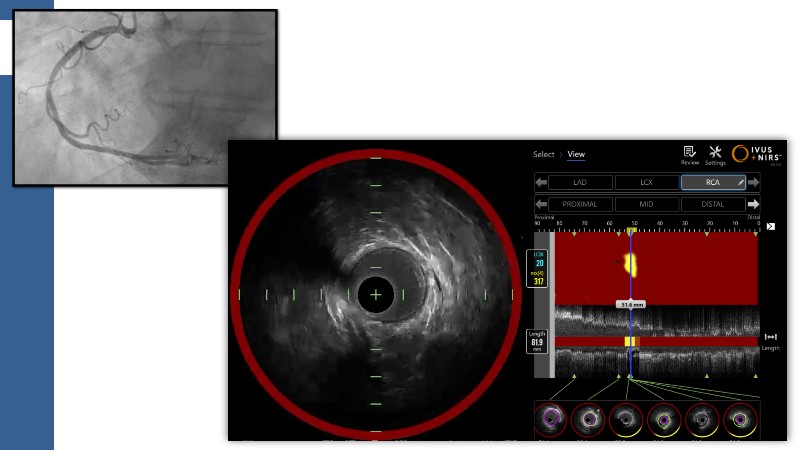

This session explores how near-infrared spectroscopy (NIRS) is redefining PCI by revealing what angiography cannot see. By identifying lipid-rich and vulnerable plaques, NIRS helps anticipate procedural risk and refine decision-making before stent implantation. The session shows how plaque composition, rather than calcium alone, can guide lesion preparation strategies, support safer stent positioning, and improve expansion. Through practical examples, it highlights how integrating NIRS with intravascular imaging and physiology moves PCI toward a more targeted, data-driven, and truly precision-based approach.

- To identify vulnerable plaques: NIRS detects lipid-rich plaques that are invisible to angiography. This allows interventionalists to anticipate complications like distal embolisation or no-reflow and adjust their approach accordingly

- To optimise lesion preparation: when NIRS reveals high lipid burden or calcific nodules, operators can choose atherectomy, intravascular lithotripsy, or specialised balloons to modify the lesion before stenting

- To improve stent placement and expansion: NIRS-IVUS guidance ensures stents are deployed in stable segments, avoiding lipid-rich or heavily calcified areas that may compromise expansion or healing